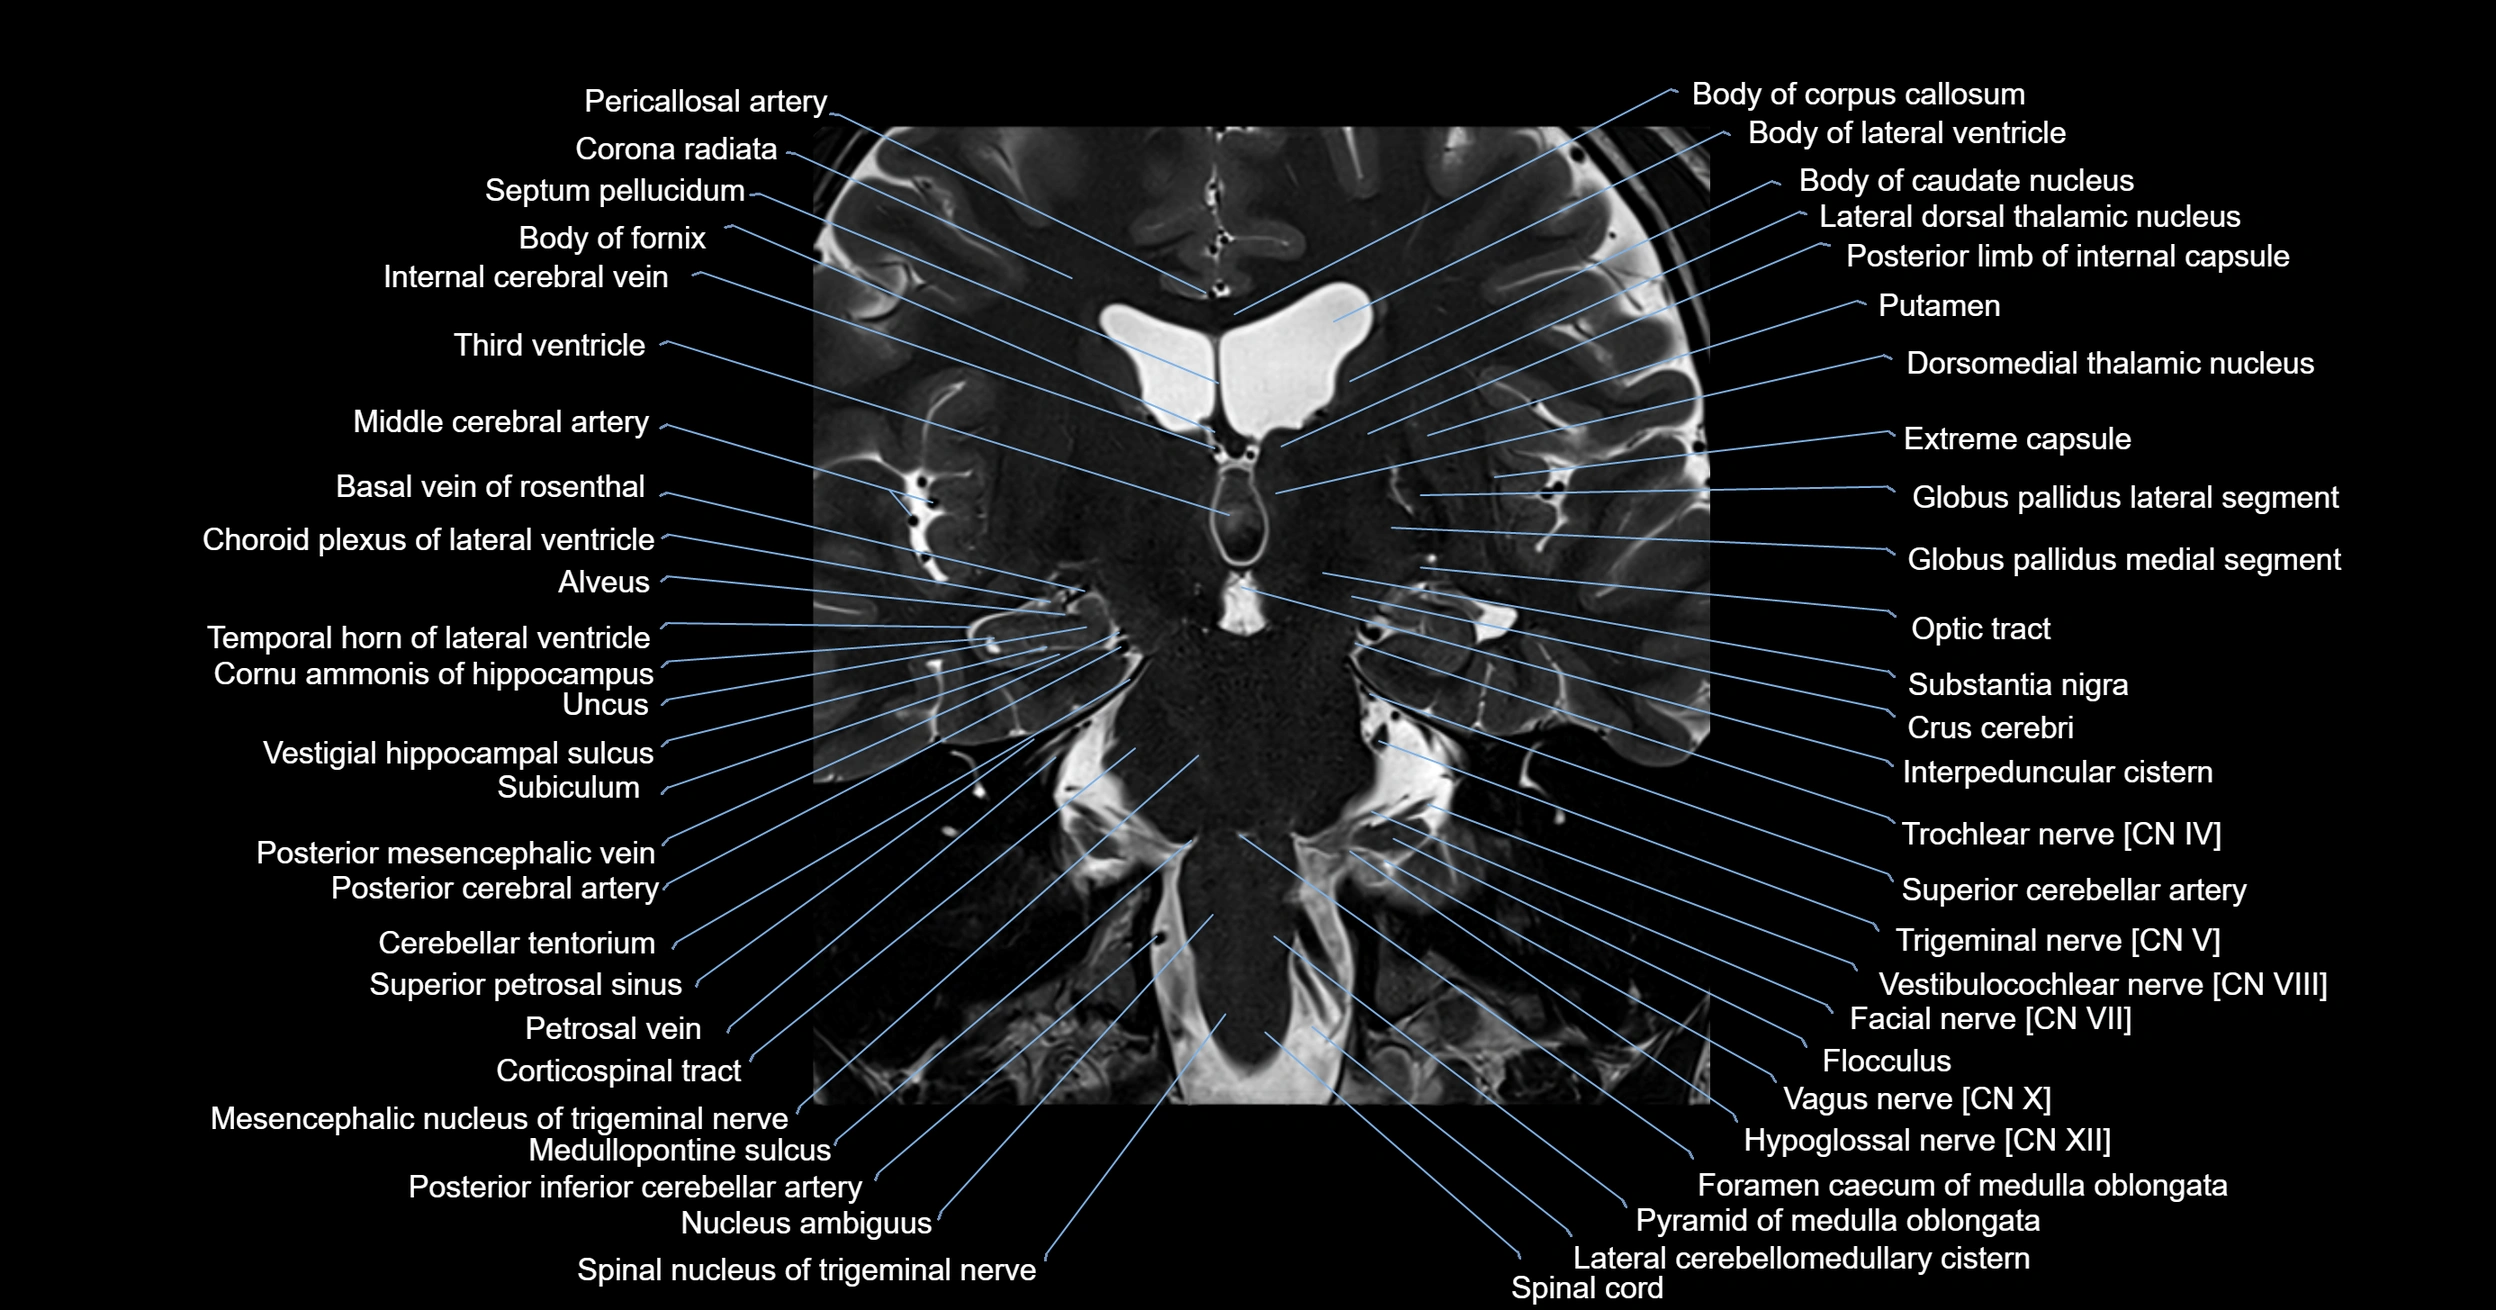

MRI images